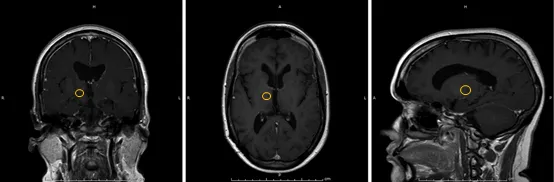

16岁女孩,双侧丘脑病变、低级别胶质瘤复发,4年间肿瘤增大,考虑到肿瘤的深部位置,医生建议进行MRI引导的立体定向方法,并进行活检,然后对病变进行激光消融。活检后,将激光纤维置于病灶中央,进行了两次热消融(31秒11 W和30秒10 W)。消融后MRI显示丘脑病变周围出现充血环,这是这些病变消融后的预期外观。没有与手术相关的并发症,患者第二天出院。病理学符合二级室管膜瘤。肿瘤在三个月和六个月时体积缩小了大约70%,并且在消融后一年几乎看不到。两年后肿瘤未复发,也未进行其他辅助治疗。

消融后1年的磁共振成像MRI,几乎看不到肿瘤